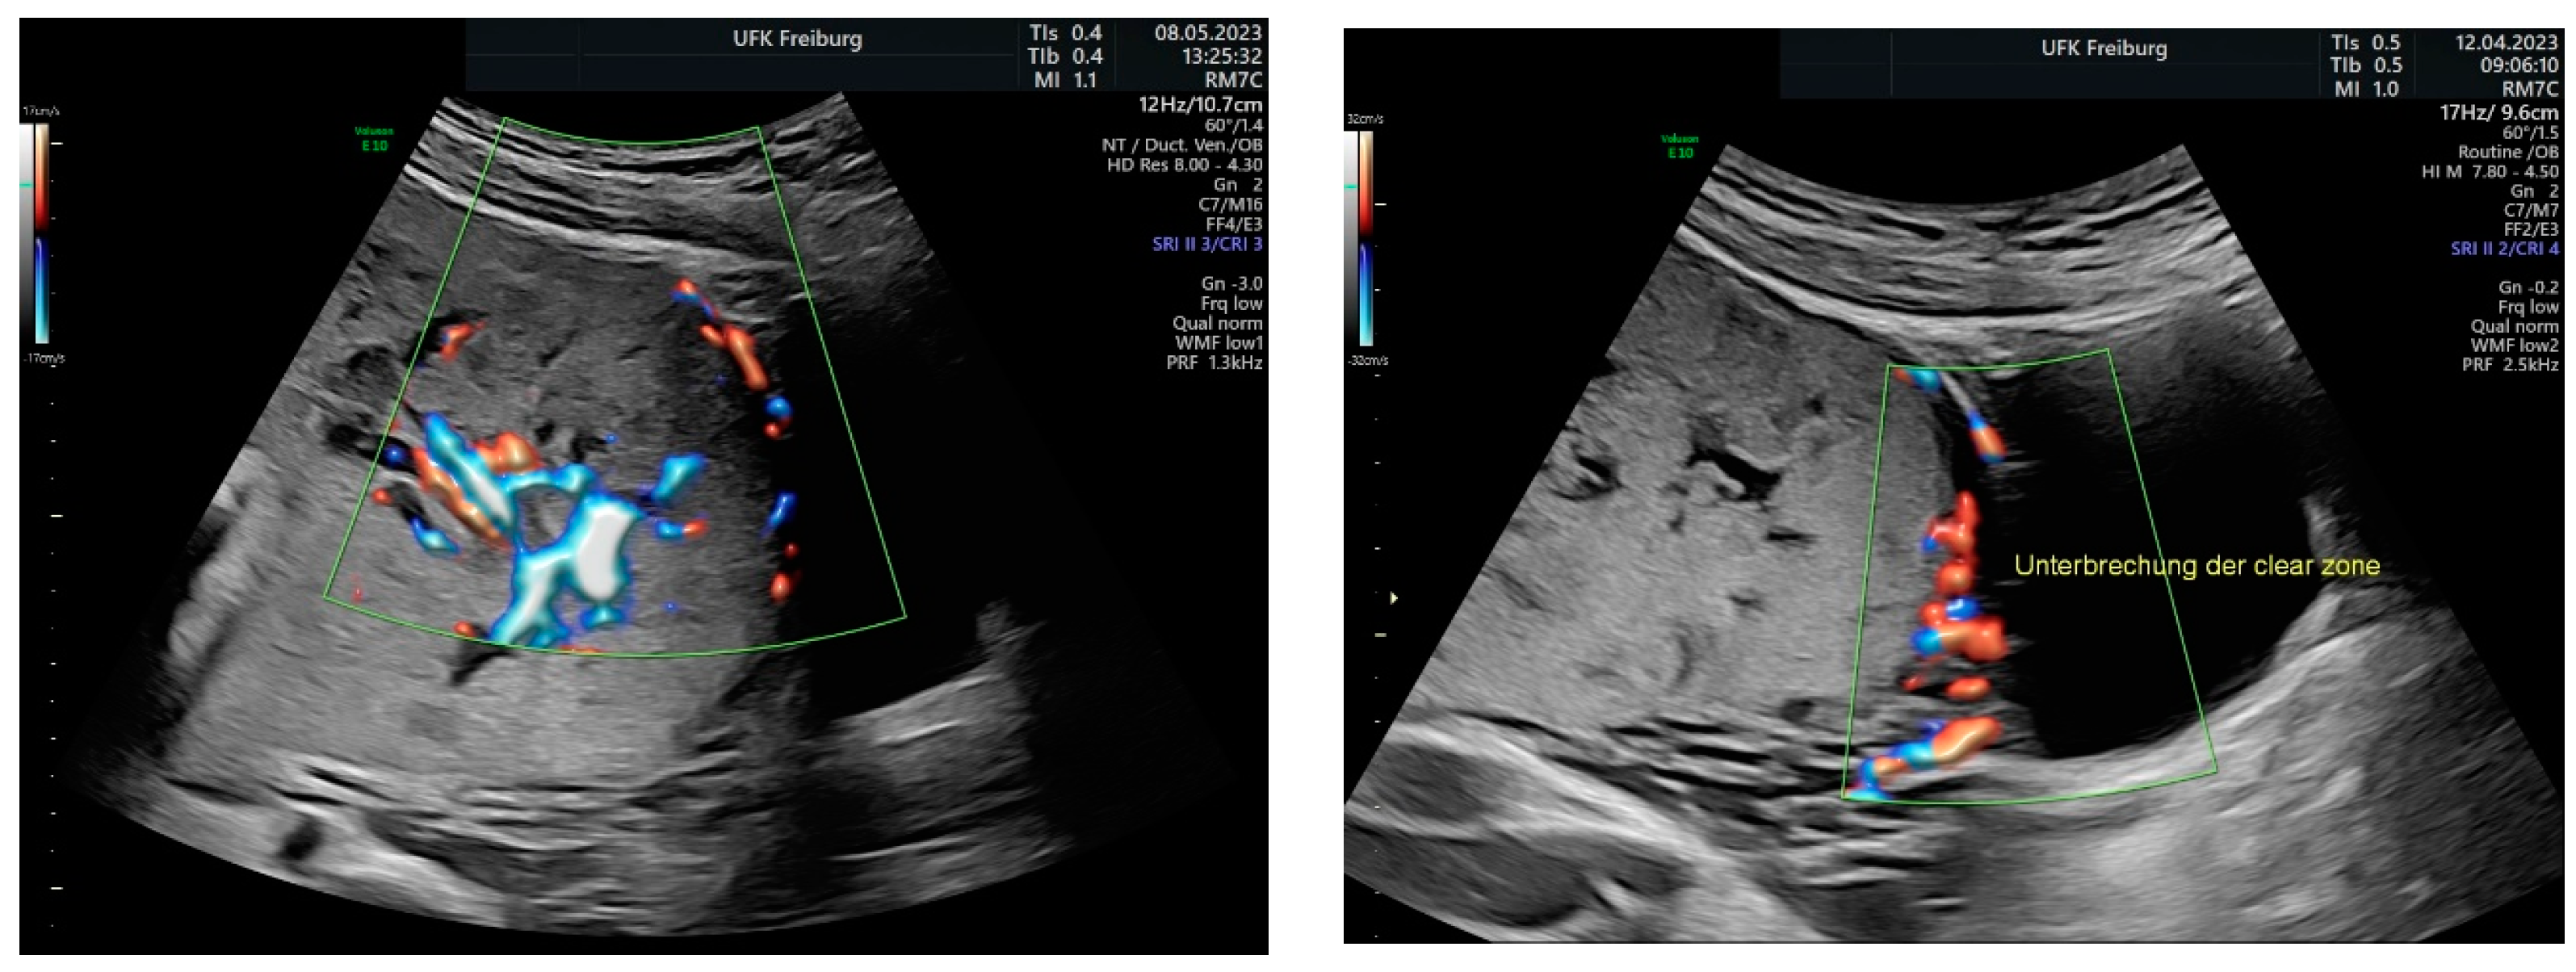

Sonographic findings (Figure 4):

Figure 4.

shows suspected placenta increta with dehiscence in the area of scar tissue from the previous uterotomy.